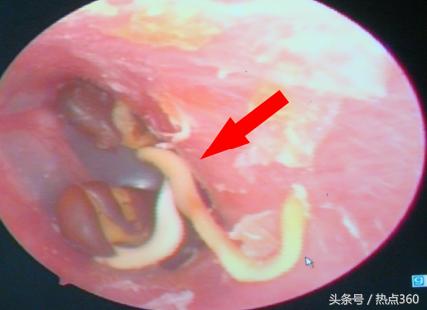

晚报6月份以《幼童塞进左鼻一粒绿豆 军医取出时已经发芽》为题曾报道过一个3岁男孩,无意中将一颗绿豆塞进鼻孔,不久长出绿豆芽的稀罕事。无独有偶,近日,252医院耳鼻喉科护士从一男孩左外耳道取出3棵发了芽的小红豆。如果没有耳内电子窥镜拍照(图1)和取出后的实物照片(图2)作证,很难让人相信。

护士采用耳内电子窥镜进行检查,看到患儿左外耳道有3个异物,异物形状好像是豆芽,感到非常奇怪。护士用镊子小心翼翼地将3个异物一一完整取出。经辨认,确认3个异物为3个发芽的小红豆。